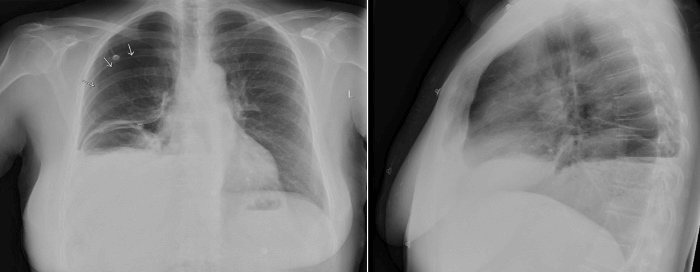

A physical examination at the ED revealed thoracic asymmetry, diminished breathing sounds on the right thorax by auscultation, and no signs of peritonitis. The patient had a tachycardia event, and the oxygen saturation level was 86%. The chest X-ray showed a pneumothorax and atelectasis in the right lobe. An atypical air configuration in the right lower thorax was observed (Figure 1). The patient’s respiratory function and hemodynamics were stable at that point. Therefore, the drainage of the pneumothorax was postponed, and an intravenous contrast-enhanced computed tomography (CT) of the thorax and abdomen was immediately performed, which showed a large pneumothorax with a mild shift of the mediastinum and heart to the left, pleural effusion, atelectasis, and a defect in the right diaphragm with intrathoracic herniation of the ascending colon and a small part of the transverse colon (Figure 2). The terminal ileum was thickened, and signs of inflammation were located in the right upper quadrant.

Figure 1: Chest X-ray before surgery.